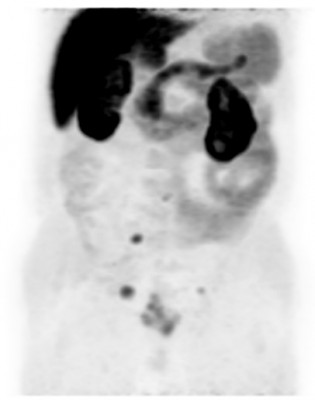

| Норма | Метастазы рака предстательной железы | Метастазы рака предстательной железы |